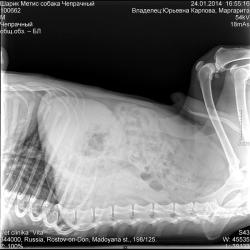

Пишет Карина: "24 января Шарик посетил ветклинику Вита. Ему сделали рентген в двух проекциях. Оказался разрыв - внимание! - ПОСЛЕДНЕГО ГРУДНОГО ПОЗВОНКА! Таз оказался практически цел. Там была трещина, но за год с помощью хондропротекторов хрящевая ткань полностью восстановилась. Врачи сказали одно слово - ЧУДО! При разрыве позвонка у него не должно быть чувствительности вообще! Но благодаря стараниям, занятиям с ним, массажу, летним заплывам в озере мы добились этого. Врачи им восхищались! Они сказали, что он восстановится, надо лечить неврологию. Нам прописали лечение - уколы и, конечно, также всё продолжать. Мочеполовая система у Шара в полном порядке. Сказали, что увеличина печень и слабовато сердечко. Нас кстати, взвесили: Шар весит ровно 20 кг)))

Все врачи сбежались и смотрели удивленно на Шарика... затем на снимки, затем снова на Шарика!))"